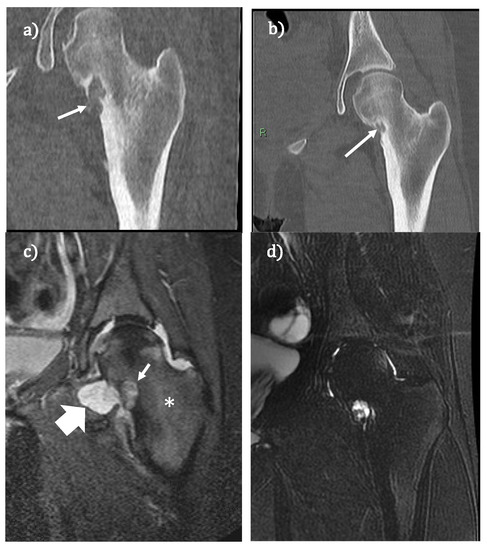

Post-Procedural Follow-Up of the Interventional Radiology’s Management of Osteoid Osteomas and Osteoblastomas

3. Osteoblastoma